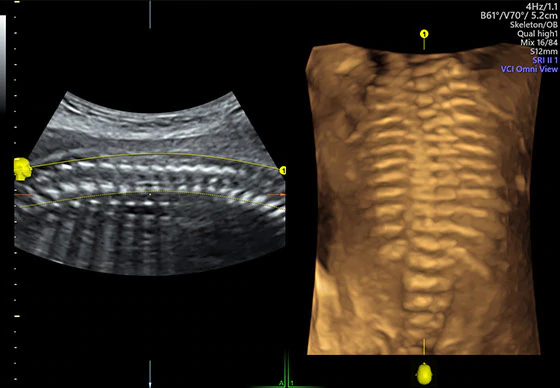

- Простота получения 3D/4D режима для того, чтобы получить больше информации и помочь в общении с пациентом.

- Функции 4D/3D Expert для применения в гинекологических и акушерских исследований;

- VOCAL II – программа, позволяющая выполнять сложные измерения в объеме;

- STIC - программа, позволяющая исследовать сердце плода с возможностью проведения ангиографии, основанной на анализе корреляции диагностической картины в пространстве и времени;

- SonoVCAD - программа, которая дает возможность диагносту исследовать сердце плода по специальным рекомендациям ISUOG в 3D-mode с моментальным доступом ко всем плоскостям;